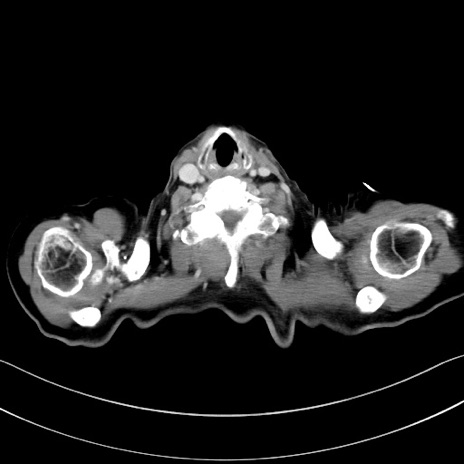

症例28(横断像)

【症例】60歳代男性

【主訴】嘔吐

【現病歴】胃癌にて胃全摘後。食思不振が悪化し、夜中に嘔吐することがある。

【既往歴】胃癌、胃全摘、脾摘、胆摘後

【データ】WBC 5900、CRP 10.56